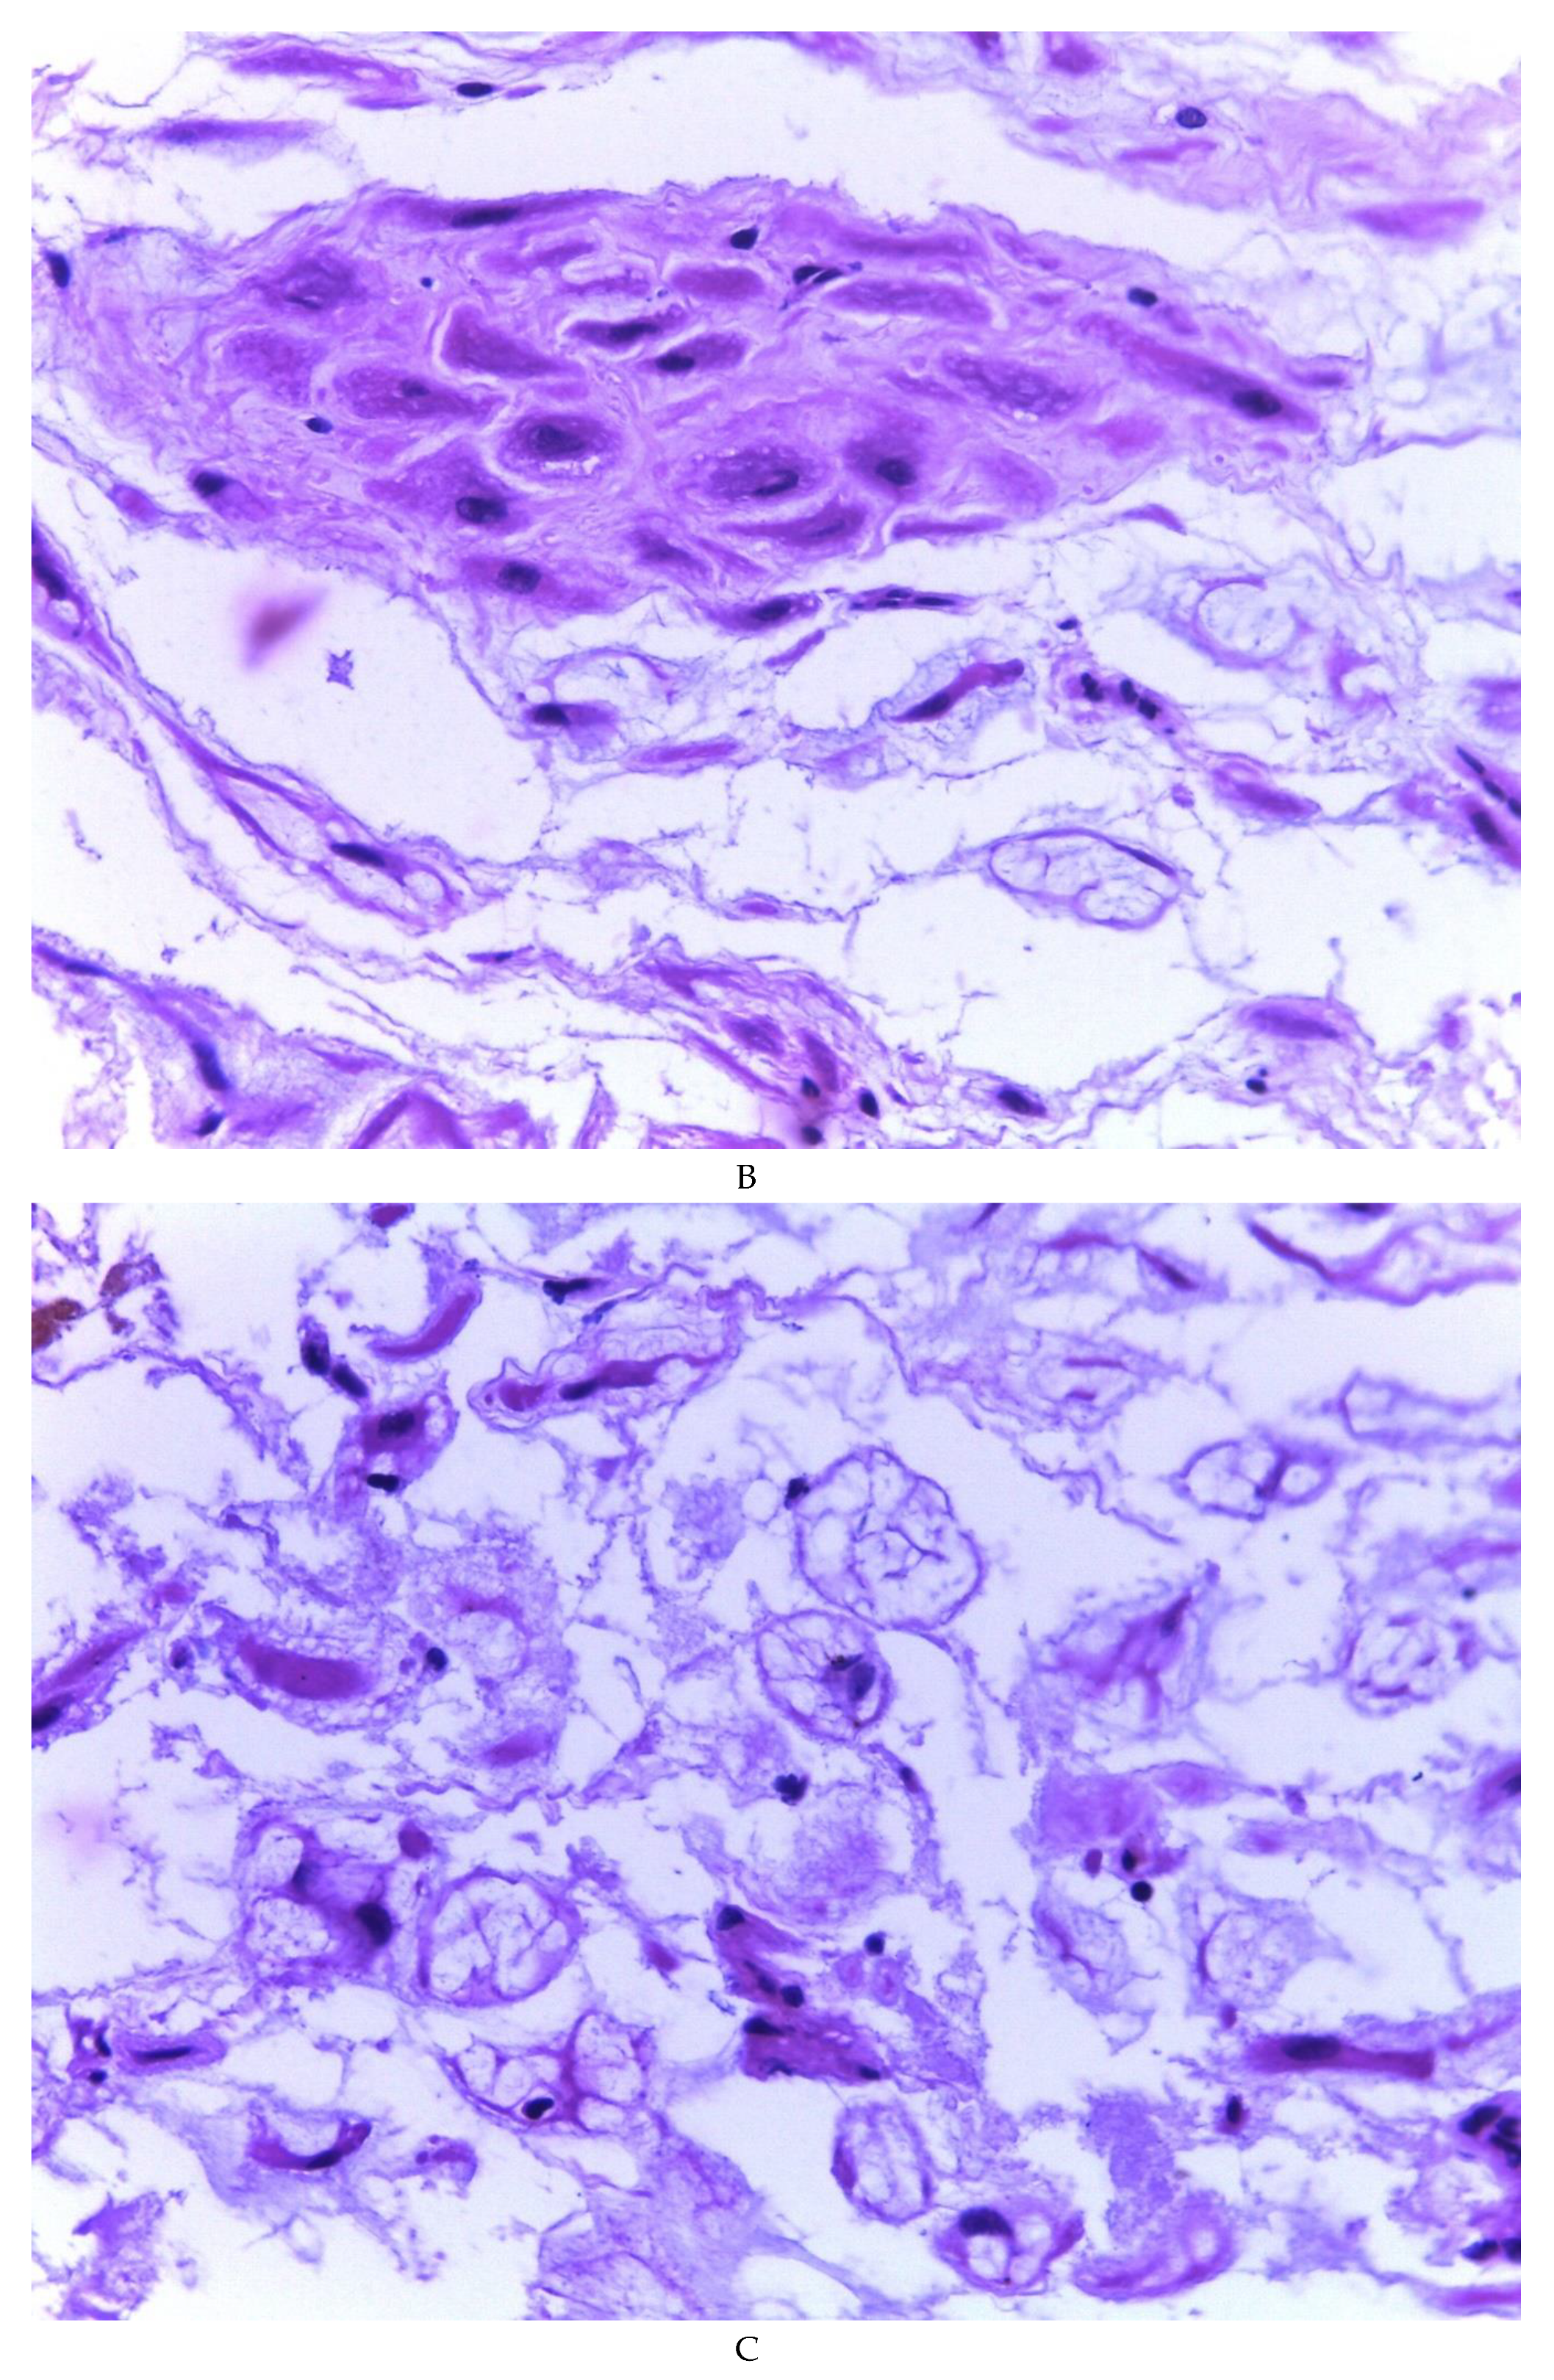

776 cases of endometriosis were collected between the two institutions participating in the study, in different anatomical sites (Table 1, Figure 1), in which 54 of them presented a myxoid stroma greater than 50% with respect to the cellularity of the samples. and that represent 6.95% of the total endometriosis examined with the following locations: omentum (4/20), ileum (2/4), ovary (14/216), parametria (2/9), soft tissues (28/235), salpingus (3/77), bladder (1/4). The clinical records of these patients were consulted and the common denominator was that the women were in the surgical (41/57) or physiological (7/39) puerperium in a period of time from 24 hours postpartum to six months after said event. Macroscopically, two different lesions were observed: the first one, which is the most frequent, presents as a non-encapsulated lesion with pushing edges of a fibromyxoid appearance; the second and less frequent, a well-defined lesion, partially or totally encapsulated, the cut surface is shiny, gelatinous in appearance, multilobed, light brown to brown in color with focal areas of recent and old hemorrhage, these lobes are separated by fibrous septa (Figure 2). Histologically, it was found in all the samples evaluated at least 50% of myxoid stroma with some fine connective tissue septa with proliferation of stromal cells (Figure 3A), which present four variants in their shape: (1) Epithelioid stromal cells of wide eosinophilic cytoplasm with round nucleus with small nucleolus (Figure 3B), (2) Pseudolipoblast-type stromal cells with moderate cytoplasm, multivacuolated in their cytoplasm that can present eosinophils or be clear cytoplasm, with central nuclei of granular chromatin (Figure 3C), (3) “pseudosignet ring” stromal cells with nucleus and cytoplasm rejected to the periphery giving the aforementioned appearance (Figure 3D) and (4) immersed spindle cells with small nucleus and barely visible nucleolus (Figure 3E); Among these cells, the epithelial component is observed, which is forming tubules that vary in diameter, ranging from small tubules and large cystic dilations of the gland that presents a layer of low cubic to cylindrical epithelium, generally with an atrophic appearance (Figure 3F). Hyaline globules were found in the glandular lumens (Figure 3G). The extracellular matrix showed a composition by glusocaminoglycans evidenced in 100% of the cases by staining present for AA (Figure 4A–C), but without staining for PAS; however, the latter stained on proteinaceous globular material in the lumen of the endometrial glands (Figure 4D). Immunohistochemistry for CD10 was positive in 100% of the stromal cells with a mild to moderate reaction in the cytoplasm and membrane with a decidual appearance (Figure 5A,B). The ER and PR showed nuclear expression in 100% of the cases, with greater intensity in the ER (Figure 5C) than in the RP (Figure 5D); both hormone receptors were expressed on endometrial epithelial cells as well as on stromal cells. The cases of myxoid endometriosis examined did not present cytological atypia suggesting any precursor lesion of epithelial or stromal origin.

Figure 4. Myxoid endometriosis – histochemical stains; A-C) Alcian blue. D) PAS, note the staining of the hyaline globules.